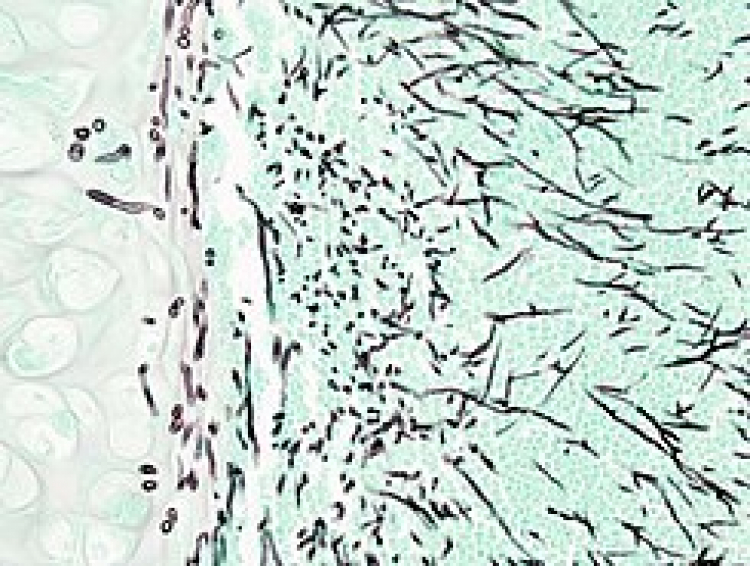

La aspergilosis es una enfermedad infecciosa causada por un hongo llamado “aspergillus”, el cual ocasiona problemas en el sistema respiratorio. Afecta principalmente a personas cuyo sistema inmune está débil, tienen asma o fibrosis quística, leucemia, alteraciones en las cavidades pulmonares, EPOC, cirrosis hepática o cáncer, o bien, siguen un tratamiento prolongado con corticoesteroides.

La Dra. Mónica Martinez Revelles, Gerente Médico de Grupo Biotoscana, señaló que existen alrededor de 200 especies de aspergillus y solamente 20 de ellas son capaces de producir enfermedades en el ser humano. Los efectos de esta enfermedad son variados y van desde tener una reacción alérgica leve a graves infecciones pulmonares. Cuando la infección se traslada a los vasos sanguíneos, provoca una nueva forma de la enfermedad llamada aspergilosis invasiva.

El hongo aspergillus se encuentra en muchos lugares, especialmente en plantas, bosques y lugares donde se acumulan hojas muertas, así que todo el mundo está expuesto. Sin embargo, aquellas personas que tienen un sistema inmune fuerte reaccionan positivamente ante el hongo. Mientras que las personas con un sistema inmune débil por diversas causas (como ser tratados por otra enfermedad, como cáncer) sus células son incapaces de reaccionar ante la infección y el aspergillus llega a los pulmones.